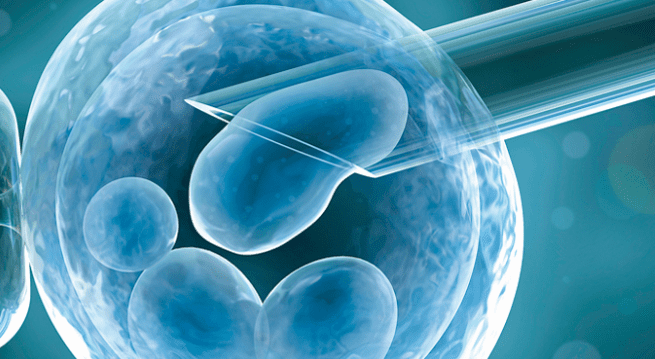

Although healthy lifestyle changes are an important piece of the fertility puzzle, these changes aren’t always enough to complete the picture. In such cases, in vitro fertilization (IVF) with ovarian stimulation is often one of the quickest and most reliable treatment options for women over 40.

During IVF, your ovaries are stimulated with injectable fertility medications so they produce multiple eggs, which are then surgically removed and fertilized in a lab with your partner’s sperm or donor sperm. The fertilized egg grows in a strictly controlled environment for up to five days before it’s transferred to your uterus, where it’s meant to implant itself in your uterine lining and continue to develop.